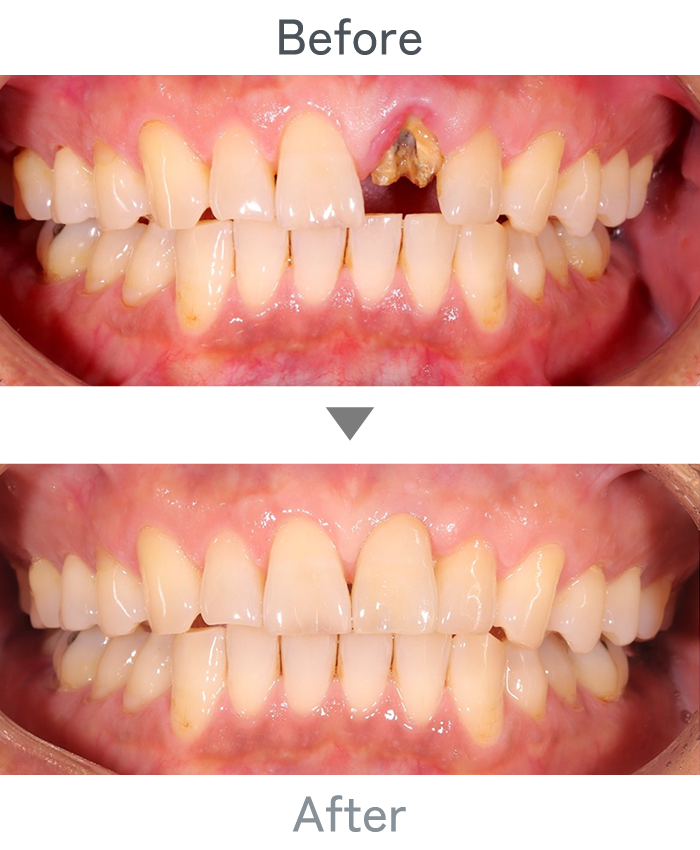

前歯のインプラント

主訴 前歯折れた

治療法 左上1番:インプラント治療

右上1番:セラミック治療

治療期間 4ヶ月半

費用 ・インプラント左上1番:300,000円

・インプラント左上1番上部構造:120,000円

・セラミック治療右上1番:120,000円

小 計:540,000円

消費税:54,000円

合 計:594,000円

※インプラント体、上部構造ともに『10年保証』

副作用

• メンテナンスが必要